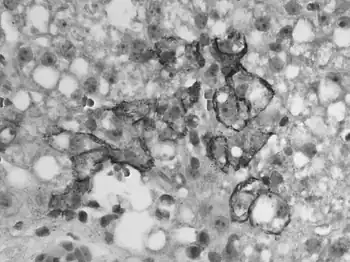

![]() | |

| Immunohistochemical staining of lymphocytic choriomeningitis virus antigens | |